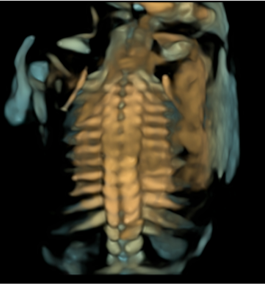

- Skeleton: siêu âm xương thai nhi, phát hiện dị tật xương

Hình ảnh thực tế trên máy siêu âm 5D SonoScape P25